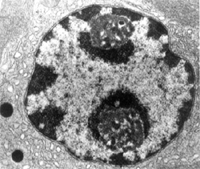

β細胞胰島β細胞膜含有磺醯脲受體及與之相偶聯的ATP敏感的鉀通道[Ik(ATP)],以及電壓依賴性的鈣通道。當磺醯脲類藥物與其受體相結合後,可阻滯Ik(ATP)而阻鉀外流,致使細胞膜去極化,增強電壓依賴性鈣通道開放,胞外鈣內流。

胞內游離鈣濃度增加後,觸發胞吐作用及胰島素的釋放。長期服用且胰島素已恢復至給藥前水平的情況下,其降血糖作用仍然存在,這可能與抑制胰高血糖素的分泌,提高靶細胞對胰島素的敏感性有關。也可能與增加靶細胞膜上胰島素受體的數目和親和力有關。